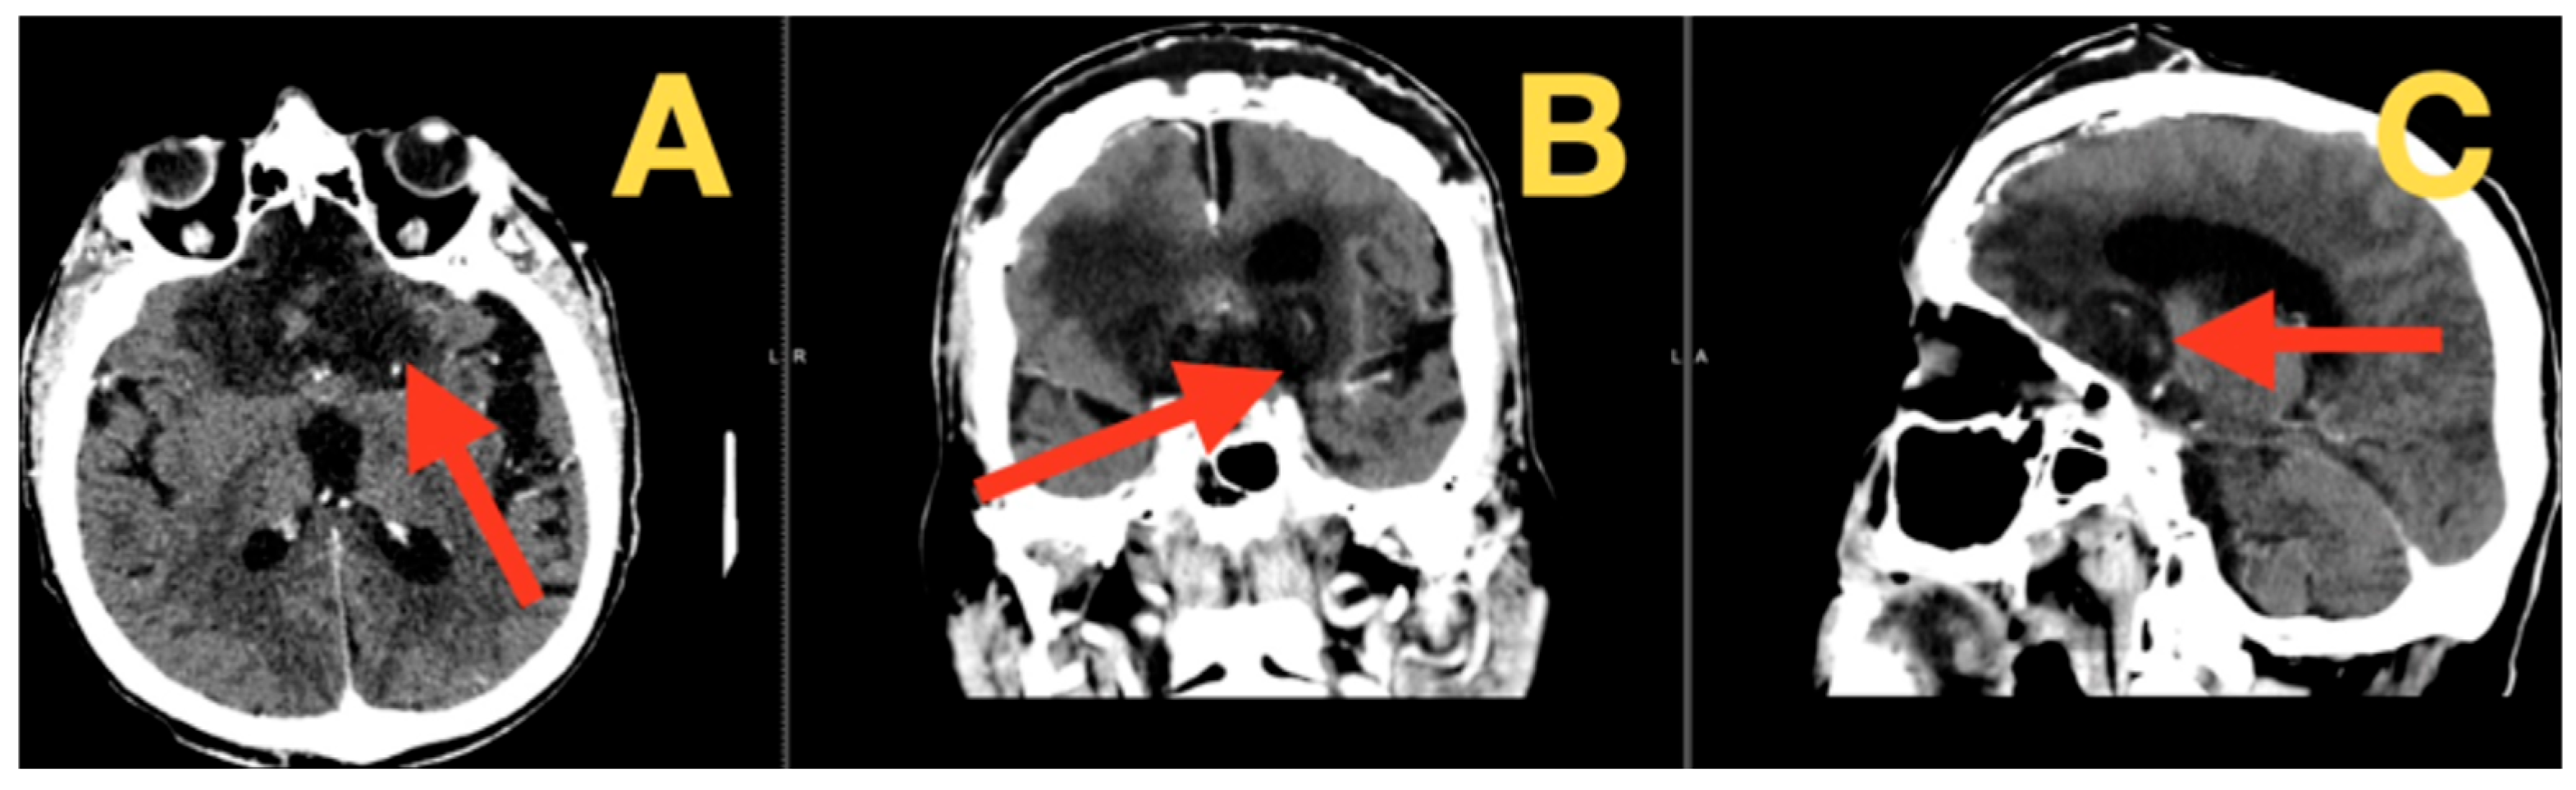

2.4. Preoperative Imaging and Quantitative Metrics